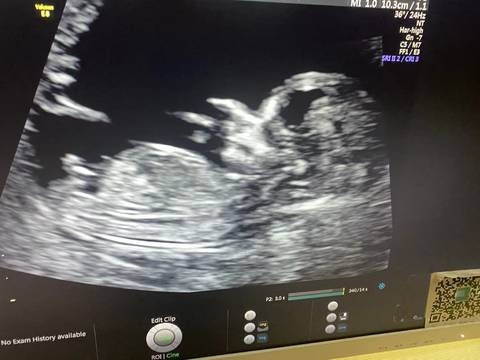

帮我看看是弟弟还是妹妹呀,我太好奇了,弟弟妹妹都是宝,好奇的睡不着????????

journal_insert_pic_1675836257journal_insert_pic_1675836258journal_insert_pic_1675836259

看起来像弟弟哦

男孩